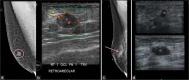

Most of male breast masses are benign with gynecomastia being the most common entity encountered. Primary male breast cancer accounts for less than 1% of the total number of breast cancer. Male breast can be affected by a variety of conditions affecting the female breast with less frequency due to the lack of hormonal influence and consequent glandular sub-development. Imaging features of male breast masses are quite similar to the female breast. Therefore, using the knowledge of the female breast and applying it may help in the diagnosis and management of male breast abnormalities. In this article, we aim to review a variety of unusual male breast masses. We discuss the demographics of male breast tumors, describe the diagnostic algorithm for evaluating male breast masses, and review the imaging features of rare breast masses and mimickers of male breast cancer.